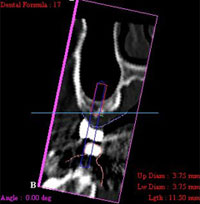

CT画像で見ると骨の厚みが1、2ミリしかなく、通常の10ミリのインプラントを入れればシミュレーションのように鼻の空洞に突き抜けてしまうばかりでなく、強い力で噛んだ時に骨折する恐れがあります。.

短いインプラントを斜めに2本入れ、奥の上顎結節に長いインプラントを1本入れて強度を確保しました。赤い部分がインプラントです。

さらに、神経損傷や麻痺のリスクを回避するため、神経や血管の位置や骨の硬さの値をより正確に把握することが可能なCTで撮影を行います。そのCTデータを3D立体構築画像検査による精密診断を必ず実施ししてから手術を行います。